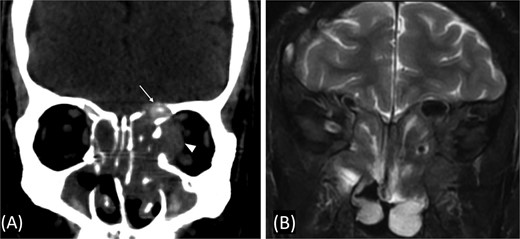

A previously healthy 36-year-old man presented to the emergency department complaining of persistent frontal headache, dizziness, and vomiting of 1 month duration, with no history of orbital complaints (e.g. visual deficits or swelling) or neurological deficits (e.g. limb weakness or seizure-like movements). On examination, the nasal endoscopy showed dry crusts filling the right nasal area. Therefore, due to the subtle symptoms’ origin, the patient was admitted, and a computed tomography (CT) scan of the head and a magnetic resonance imaging (MRI) of the brain were scheduled. The head CT scan revealed complete opacification of the maxillary, ethmoid, frontal, and sphenoid sinuses with bone destruction affecting the left lamina papyracea and roof of the ethmoid air cells (Fig. 1A). The brain MRI demonstrated similar findings with intra-orbital extension resulting in left global proptosis, which triggered concerns regarding fungal rhinosinusitis (Fig. 1B). Accordingly, the patient underwent functional endoscopic sinus surgery (FESS) with a right frontal craniotomy and partial removal of the infected brain tissue on the fourth day of his presentation. Specimens from both surgical sites were sent for pathology and cultures during the surgery. The histopathological results confirmed the diagnosis of CGIFRS, and A. flavus was found in the tissue culture. Postoperatively, the patient was stable, and intravenous antifungal treatment (amphotericin B and voriconazole) and high-dose steroid administration (dexamethasone) were started promptly following confirmation of CGIFRS via pathology. One week after the surgery, the patient’s condition suddenly deteriorated: he had a right fixed dilated pupil and spikes of fever. An urgent brain MRI with contrast was performed, which showed an intracranial abscess, and a significant midline shift to the right side (Fig. 2A and B). The patient, therefore, had a right decompression craniotomy and remained intubated and ventilated in the intensive care unit to receive the maximum medical therapy. However, despite this intensive treatment, the patient’s condition continued to worsen, and he ultimately died after 2 weeks.

(A and B) Brain MRI with contrast showing signs of intracranial abscess in the left side with mass effect and midline shift to the right side.